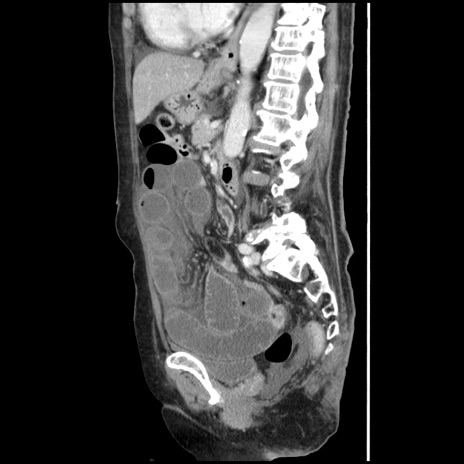

横断像

【症例】80歳代女性

【主訴】腹痛

【現病歴】8時間前から腹痛あり来院。

【既往歴】糖尿病、脂質異常症、子宮体癌にて子宮全摘術

【身体所見】意識清明・会話良好だが腹痛で苦悶様、全腹部にわたって反跳痛と圧痛あり

【データ】WBC 13600、CRP 0.14、LDH 224、CK 90